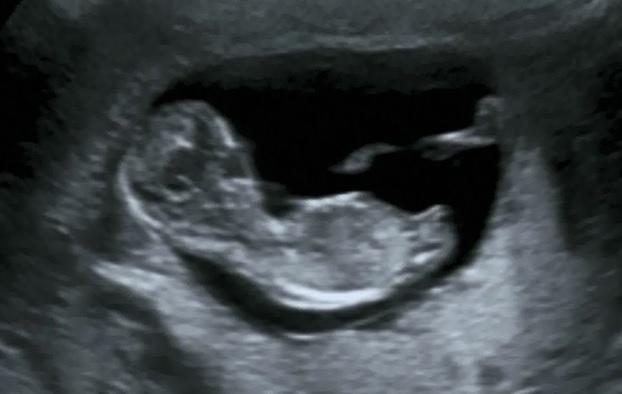

11 weeks and 6 days.Attachment 20230Attachment 20229

Looks girly to me but extremely early so guesses don't mean much at this gestation.

still way early, but looks girly to me

I'm thinking girl

I actually think boy. But it is really early.